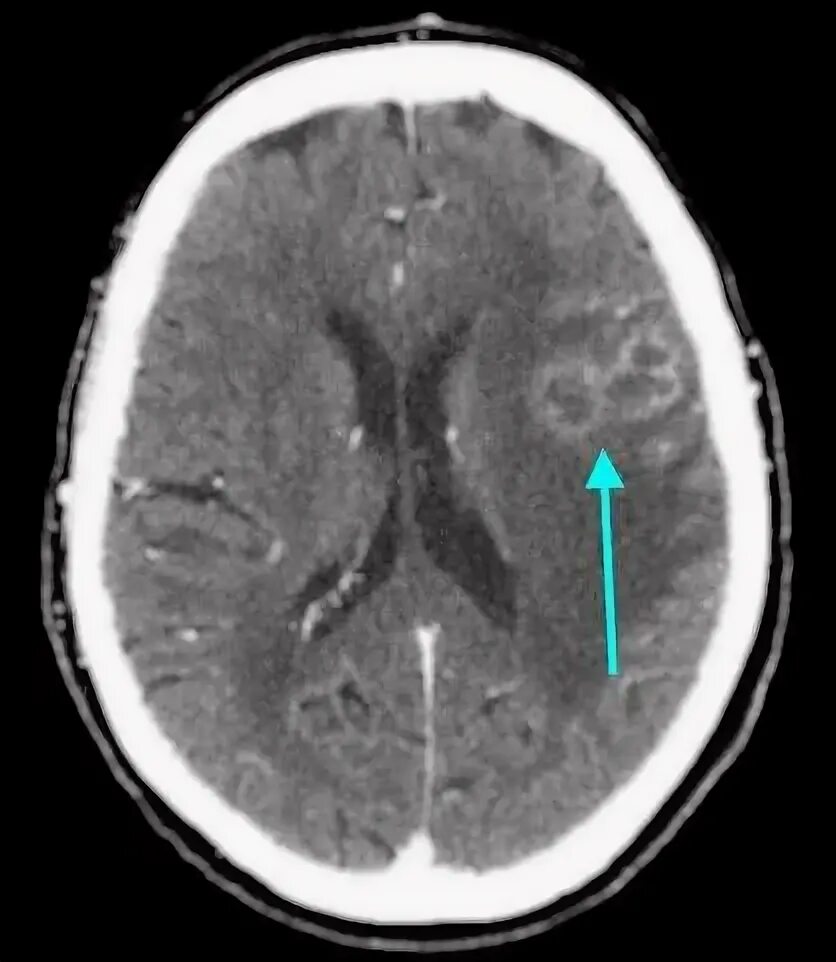

Отек мозга метастазы